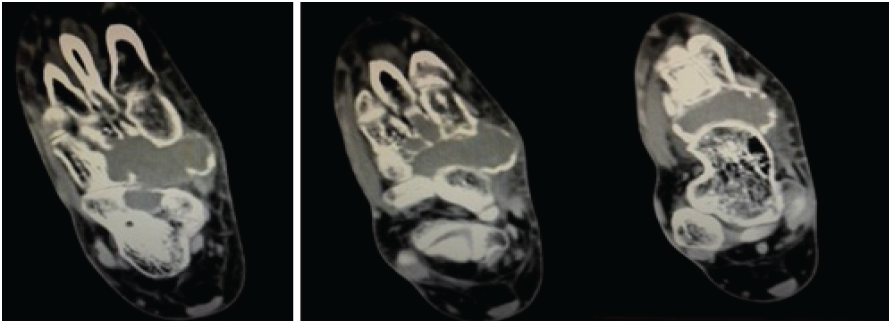

Routine radiological investigations revealed a large globular lesion in the navicular bone (Fig. 2). Computed tomography scan (Fig. 3, 4) and magnetic resonance imaging (Fig. 5) modalities revealed an expansile lesion in the navicular bone lobulated extension of lesion on the plantar aspect and adjacent tarsal bones (cuneiform, cuboid) and intertarsal joints. We thus had a suspicion of a malignant lesion? Round cell tumour? Ewing’s sarcoma. On following up with histopathology, the histopathological report of lesion determined giant cell tumor (GCT).

Figure 5: Magnetic resonance imaging scans indicate hypointense lesion in the navicular bone.